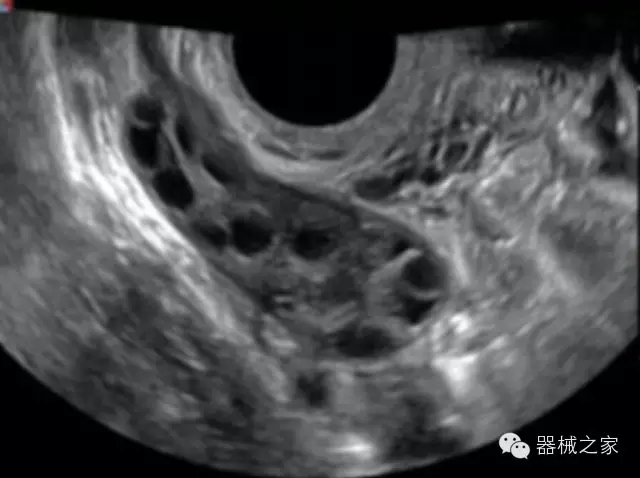

品牌:開(kāi)立(SONOSCAPE)

公司簡(jiǎn)介:

深圳開(kāi)立生物醫(yī)療科技股份有限公司作為中國(guó)民族醫(yī)療產(chǎn)業(yè)的優(yōu)秀引導(dǎo)者,自成立伊始,一直致力于臨床醫(yī)療設(shè)備的研發(fā)和制造,產(chǎn)品涵蓋醫(yī)用數(shù)字超聲診斷系統(tǒng)、電子內(nèi)窺鏡系統(tǒng)、全自動(dòng)五分類血液細(xì)胞分析儀以及自主研發(fā)的探頭群。

官方網(wǎng)站:www.sonoscape.com.cn

經(jīng)典產(chǎn)品:S8EXP

臨床圖片賞析

產(chǎn)品特點(diǎn)

優(yōu)異的成像技術(shù)

·亞陣元技術(shù):獨(dú)有的亞陣元技術(shù),對(duì)獨(dú)立晶片做二次切割,減少旁瓣偽像,增加臨床診斷的準(zhǔn)確性;

·μ-Scan微米成像技術(shù):開(kāi)立獨(dú)有的μ-Scan技術(shù),還原出真實(shí)細(xì)膩、層次對(duì)比優(yōu)異的二維圖像;

·倒相諧波成像技術(shù):倒相諧波技術(shù)在去除基波信號(hào)的基礎(chǔ)上獲取兩倍二次諧波信號(hào),提高組織圖像的對(duì)比分辨力;

·智能微血流成像技術(shù):智能微血流捕捉技術(shù)可以提取出隱藏在背景噪聲中的弱血流信號(hào),大大提高低速血流的敏感性;

全面的臨床解決方案

超聲科常規(guī)領(lǐng)域應(yīng)用

·移植S40高端臺(tái)式彩超高端平臺(tái)技術(shù),滿足超聲科腹部、淺表、婦產(chǎn)科、心血管、肌骨等應(yīng)用,提供超聲科完美解決方案;

·實(shí)時(shí)的彈性成像技術(shù):提高了小器管(乳腺,甲狀腺、淺表軟組織腫瘤等)疾病鑒別診斷;

·IMT血管內(nèi)中膜自動(dòng)測(cè)量:為血管性疾病評(píng)估提供了有效的評(píng)估手段;

·心功能綜合指數(shù)(TEI指數(shù)):用于左、右心室整體心臟收縮舒張功能評(píng)估的測(cè)量方法;

·全方位可調(diào)M型:有利于更好的觀察心腔大小及室壁階段性運(yùn)動(dòng)的異常情況;

·組織多普勒成像(TDI):TDI可定量評(píng)價(jià)心肌運(yùn)動(dòng),判斷是否有局部病變,還可評(píng)價(jià)早期的舒張功能;

·高效3D/4D成像技術(shù):高速的4D幀頻,豐富的3D成像模式,智能斷層切片功能;

POC領(lǐng)域解決方案

·外觀小巧;

·穿刺增強(qiáng)技術(shù):可有效提高進(jìn)針區(qū)圖像分辨率,提高進(jìn)針亮度,全面提高一次性穿刺的成功率;

全面的術(shù)中探頭解決方案

·小凸探頭:開(kāi)放性手術(shù),實(shí)時(shí)監(jiān)測(cè)病灶位置,提高手術(shù)成功率,可應(yīng)用于麻醉科、肝膽外科、腫瘤外科、神經(jīng)外科、泌尿外科等手術(shù);

·L型線陣探頭:高分辨率圖像,清晰顯示病灶位置,提高手術(shù)成功率,可應(yīng)用于麻醉科、胸外科、肝膽外科、腫瘤外科、神經(jīng)外科、泌尿外科等應(yīng)用;

·MPTEE:經(jīng)食道探頭術(shù)中監(jiān)測(cè),可測(cè)量心臟前負(fù)荷(左室舒張末期大小、右房大?。?、心排血量、后負(fù)荷、收縮功能、室壁運(yùn)動(dòng)分析、肝靜脈血流(與中心靜脈壓相關(guān))等,術(shù)后還能及時(shí)評(píng)估手術(shù)效果評(píng)估;

·獨(dú)有的大角度及實(shí)時(shí)溫控技術(shù),能同一切面顯示宮頸及宮體,有效減低了患者的痛苦,及保護(hù)粘膜保證了醫(yī)療安全;

高效的人機(jī)工程學(xué)設(shè)計(jì)

·15‘’高清醫(yī)用顯示器;

·內(nèi)置雙探頭接口;

·可升降臺(tái)車,1拖3探頭擴(kuò)展器;

·m-Tuning一鍵優(yōu)化;

CFDA注冊(cè)證編號(hào)

·粵食藥監(jiān)械(準(zhǔn))字20132230491